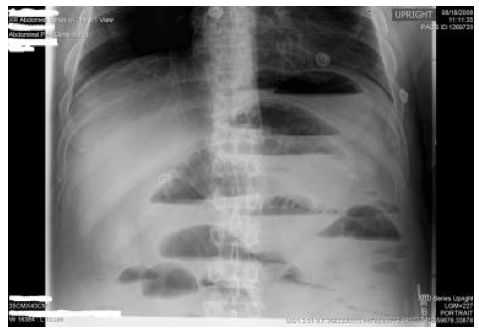

X-ray shows air-fluid levels (Caused by distension)

Could be CD, or something is obstructing the abdomen